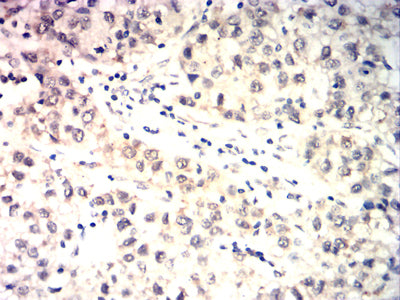

Immunohistochemical analysis of paraffin-embedded human baldder cancer tissues using TDP43 mouse mAb with DAB staining.